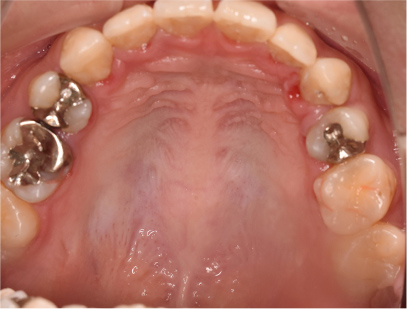

症例03

前歯が出ている症例

上の歯が出いることを主訴として来院されました。

通常通り検査を行い、「上下顎前突」と診断されました。

治療計画

上下4番目の歯を抜歯してそのスペースを利用して上の前歯を内側に移動させる事としました。

矯正の種類

上は裏側矯正

下は表側からの白い矯正装置(セラミック)

治療後

• 矯正治療後の横顔

• 正面

• 上側

• 下側

• 左側

• 右側

コメント

治療前の写真と比べると上下の前歯は後方に下がりました。

そのために、鼻の下の膨らみもすっきりして、下唇も薄くなることができました。

治療期間は2年と6か月を必要としました。